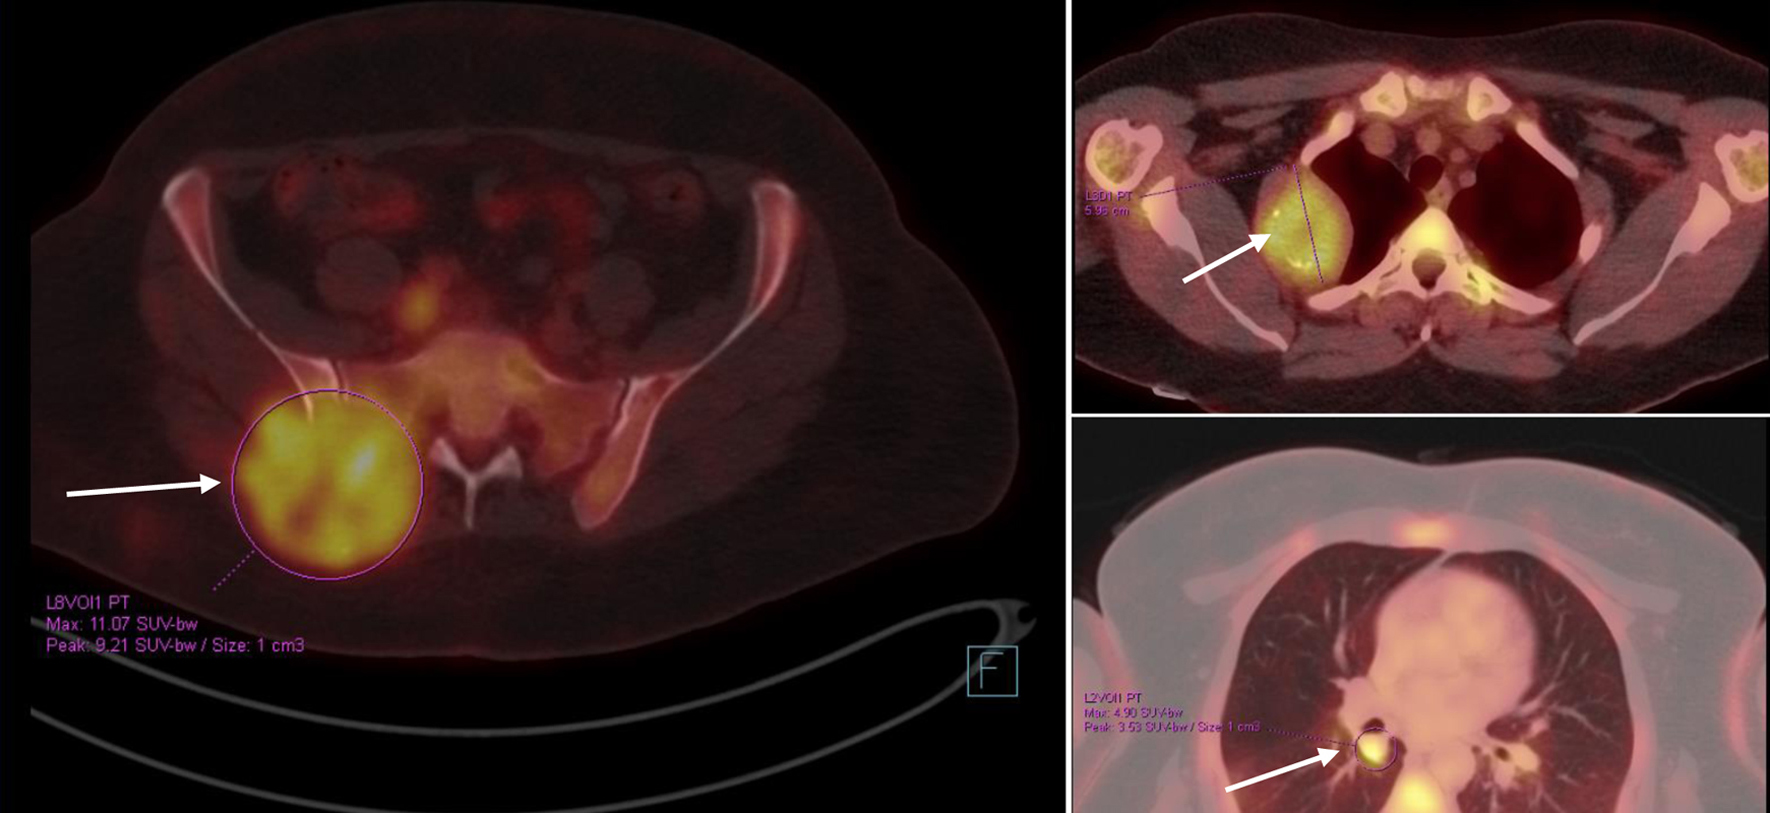

The patient was kept on regular follow-up with imaging and Pap smears, until August 2020, when she was discovered to have an enlarging pulmonary nodule in the right upper lobe, which on subsequent imaging showed interval enlargement, along with new multiple bilateral pulmonary nodules indicating pulmonary metastases (Fig. 2). Additionally, prominent right hilar lymph nodes were noted. Furthermore, a lytic bony lesion involving the second right rib, accompanied by an associated soft tissue component was consistent with a metastatic deposit. In addition, there was a small lytic lesion involving the left seventh rib. Positron emission tomography (PET)/CT scan confirmed the widespread metastatic disease (Fig. 3). β-hCG level was repeated then and was still within normal levels (0.111 mIU/mL). A biopsy from the right sacral mass confirmed the presence of metastatic leiomyosarcoma.

![]() Click for large image | Figure 2. First disease progression shown on CT scan with contrast, manifested with multiple bilateral pulmonary nodules and two prominent right hilar lymph nodes, with multiple scattered destructive lytic bony lesions (arrows) (August 12, 2020) (a: coronal, bone window; b, c: axial, lung window). CT: computed tomography. |

![]() Click for large image | Figure 3. PET/CT scan showing widespread metastatic disease (arrows) (September 10, 2020). Beta-hCG level was within normal levels. Beta-hCG: beta human chorionic gonadotropin; CT: computed tomography; PET: positron emission tomography. |